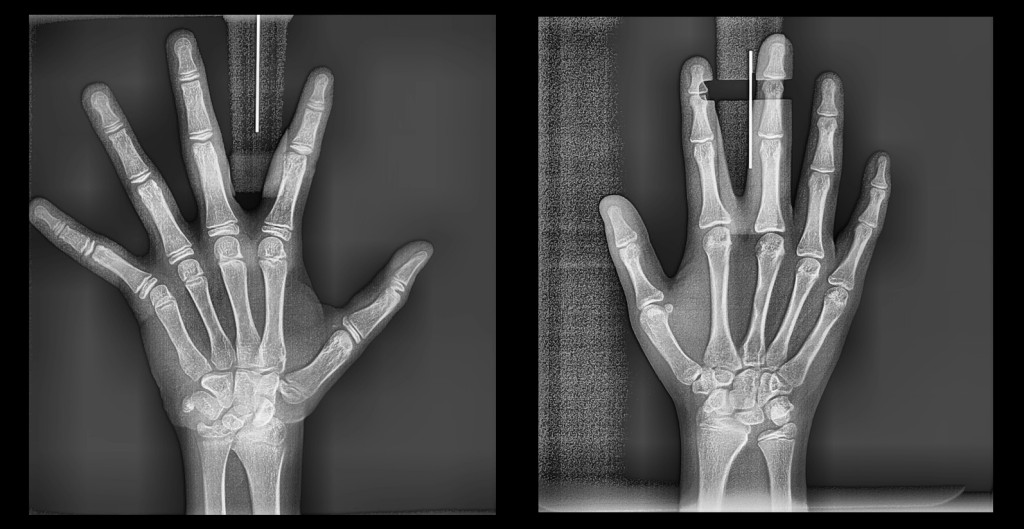

Más allá de los dientes y huesos, esta radiografía nos dice cuando puede desarrollarse aun un niño o adolescente, y cuándo aprovechar ese potencial.

CARPAL